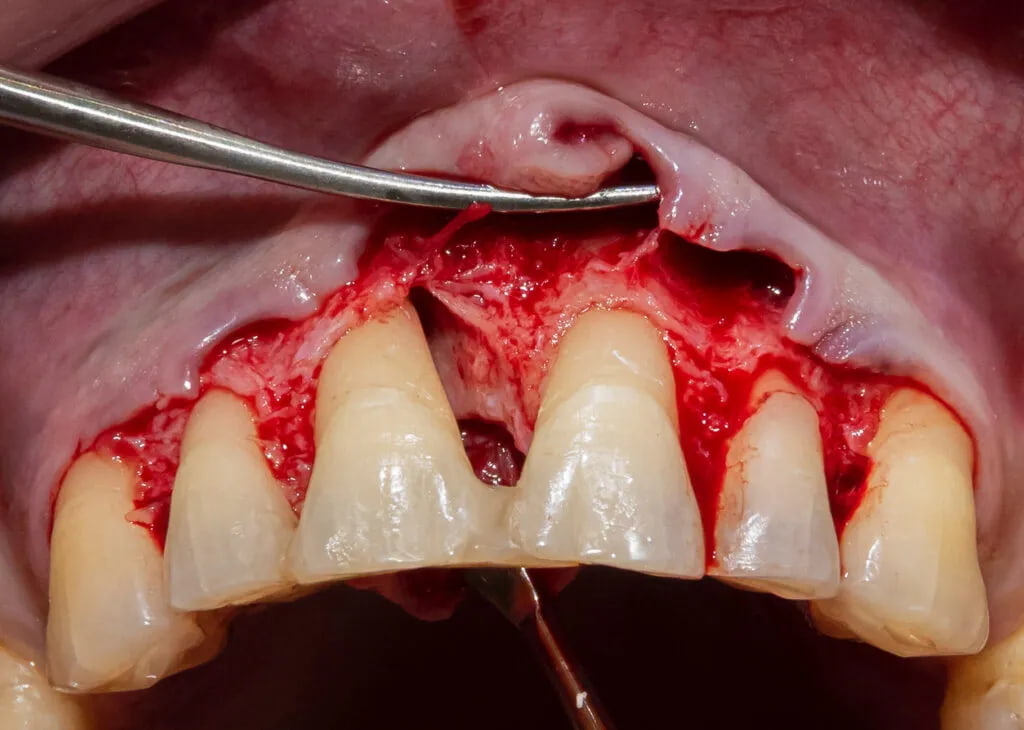

Leczenie plastyczne pojedynczych recesji dziąseł

Dużym wyzwaniem jest leczenie ubytków tkanek miękkich w strefie estetycznej. Aby uzyskać zadowalające rezultaty, poza całkowitym pokryciem recesji należy odtworzyć tkanki o właściwym kolorze i odpowiedniej powierzchni.

Leczenie plastyczne mnogich recesji dziąseł

Decyzja dotycząca leczenia mnogich recesji dziąseł powinna być poprzedzona wnikliwą analizą każdego przypadku. To niezwykle ważne, ponieważ nie tylko całkowite pokrycie recesji, ale także jakościowe wyniki estetyczne są kluczem do osiągnięcia optymalnych efektów terapii.

Zabiegi z zakresu periodontologicznej chirurgii regeneracyjnej pozwalają na pełne odtworzenie utraconych w przebiegu zapalenia przyzębia tkanek twardych i miękkich. Tym tym samym poprawiają rokowanie dotyczące zachowania zęba lub zębów.